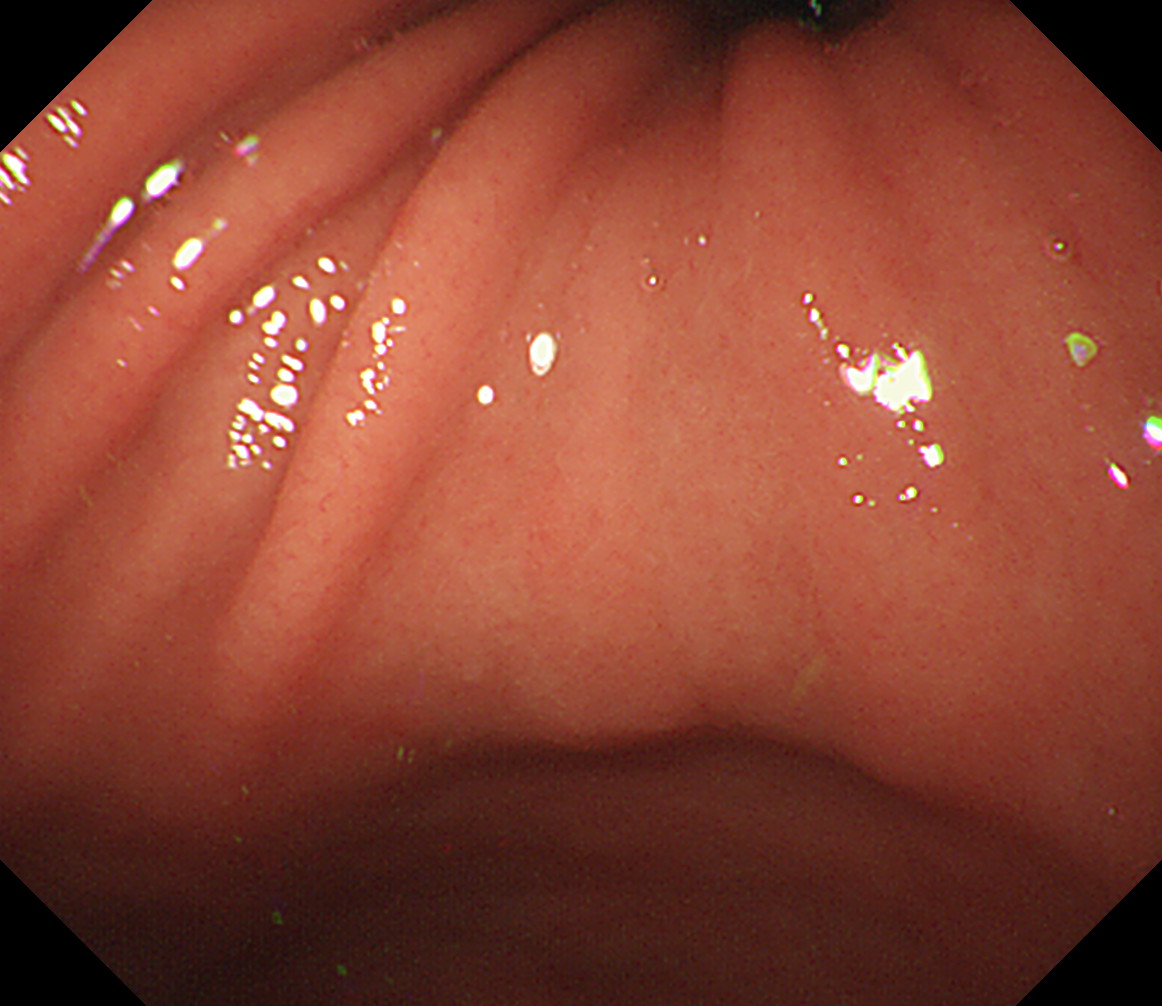

15 体中部小弯 接線になり見逃しやすい部位です 体中部小弯

16 体上部小弯 接線になり見逃しやすい部位です 体上部小弯